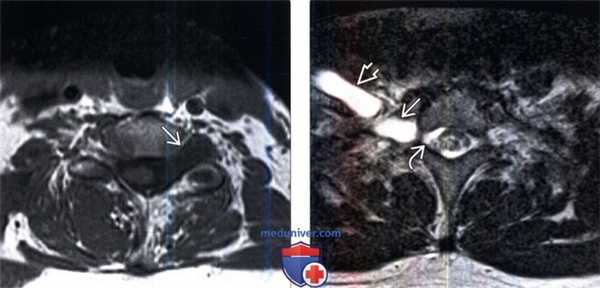

(Слева) Аксиальный срез, Т1-ВИ, пациент с травматическим отрывом корешка. Классическая МР-картина старого отрыва корешка с формированием псевдоменингоцеле.

(Справа) Аксиальный срез, Т2-ВИ: патологическое экстрадуральное жидкостное скопление в спинномозговом канале на уровне Т1, свидетельствующее об отрыве корешка с формированием псевдоменингоцеле. Обратите внимание на значительное утолщение вентральных первичных ветвей С8 и Т1 вследствие тяжелого тракционного повреждения плечевого сплетения.